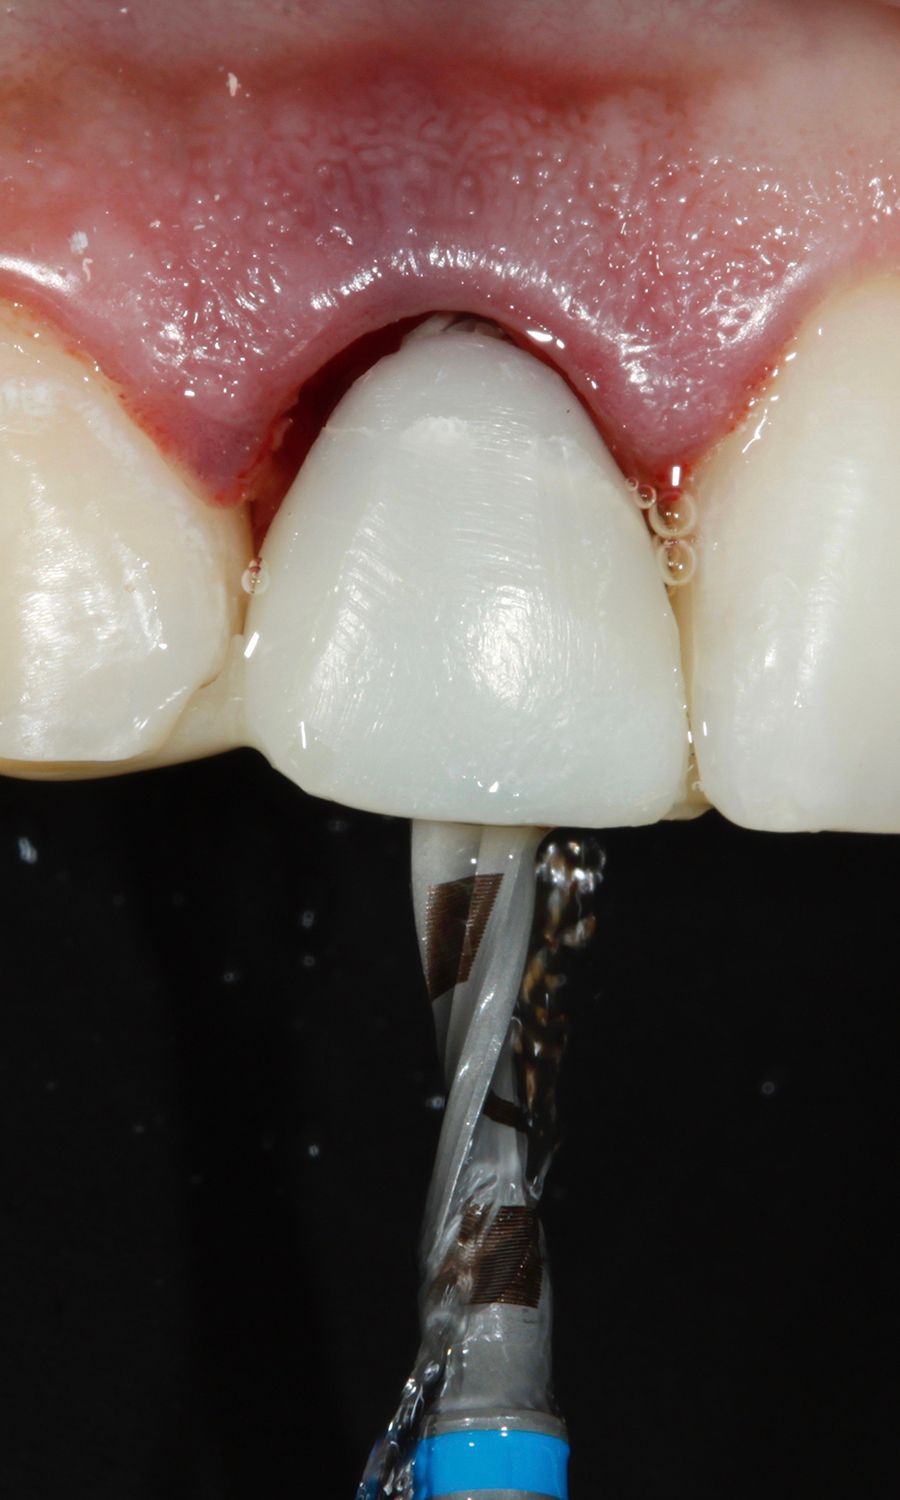

Furthermore, the subgingival segment was contoured with flowable composite in accordance with the slim concave emergence profile concept, contributing to the shaping of the gingival tissues (Figs. 20,21).

The final prothesis was created through a digital workflow. A digital impression was acquired using the Straumann® Virtuo Vivo™ Intraoral Scanner. The intraoral scanner accurately captured the 3D implant position facilitated by a scanbody attached to the BLX implant (Fig. 22).Next, an STL file was generated. We then used CARES® Visual, acknowledged as one of the dental industry's most flexible and powerful CAD/CAM software platforms for the purpose of designing dental restorations, to design the crown of #12 (Fig. 23).